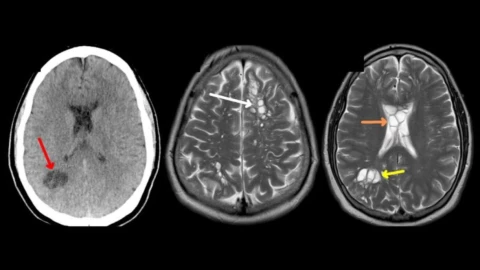

Durante la evaluación, los médicos revisaron sus signos vitales y realizaron un examen neurológico, sin encontrar anomalías aparentes. Sin embargo, la persistencia de las migrañas llevó a los especialistas a realizar una tomografía computarizada, donde identificaron múltiples “focos quísticos” en ambos hemisferios cerebrales. El hallazgo obligó a ingresar al hombre de urgencia al hospital y a realizar estudios más exhaustivos, incluida una resonancia magnética que confirmó las lesiones.

Diagnóstico inesperado: neurocisticercosis por Taenia solium

Tras sospechar de una infección parasitaria, los médicos descartaron la cirugía y remitieron al paciente a Infectología. Allí, los análisis de sangre detectaron anticuerpos que confirmaron cisticercosis. Asimismo, se identificaron anticuerpos contra Taenia solium, un parásito intestinal del ganado que puede provocar teniasis y cuya forma larvaria es responsable de la cisticercosis.